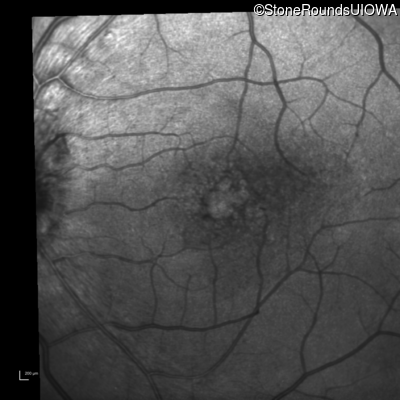

Infrared Fundus Photograph - Right - 20/30 -2